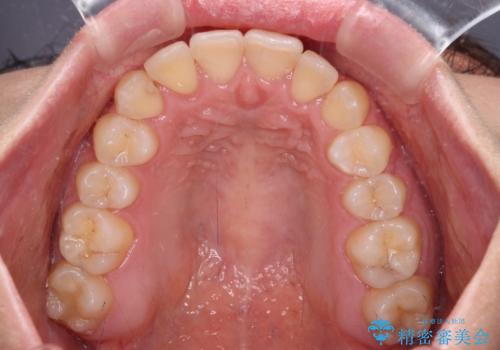

前歯のクロスバイトを短期間で解消 目立たないワイヤー矯正

- 前歯のクロスバイトを治したいとのことで来院された患者様です。

できる限り楽して、短期間で治したいとのことで、ワイヤー装置にて矯正治療を行うこととしました。